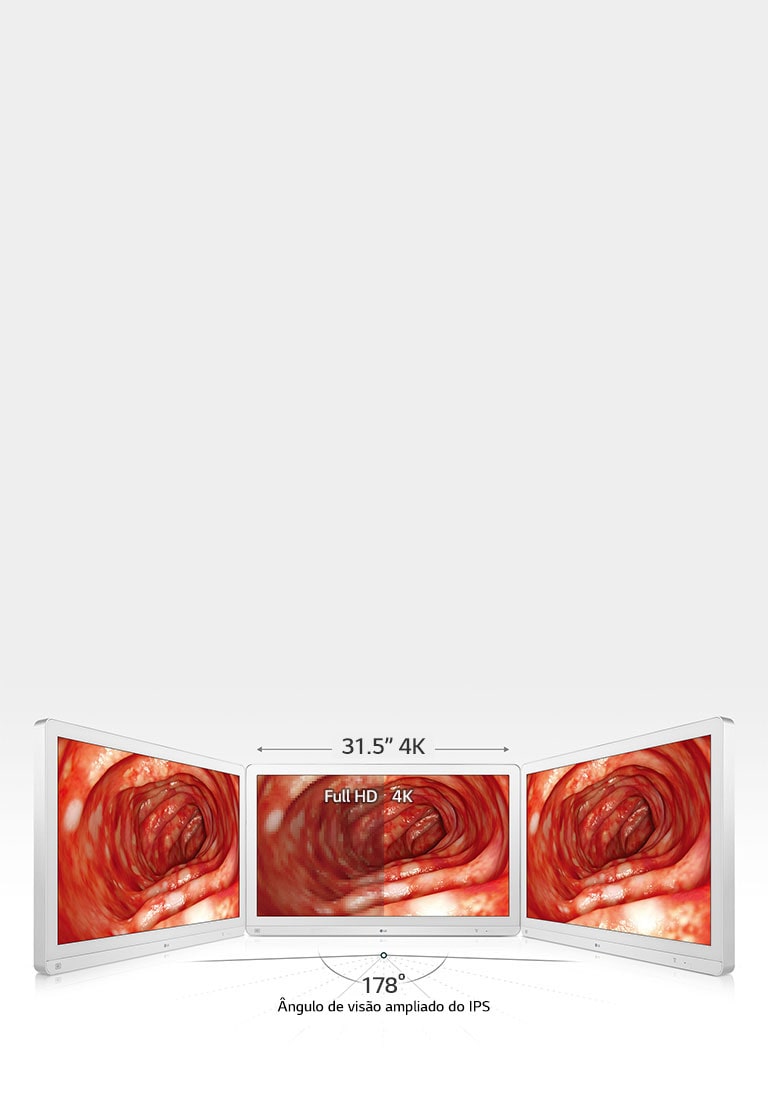

31.5

3840 x 2160

Ângulo de visão (CR≥10)

178º(R/L), 178º(U/D)